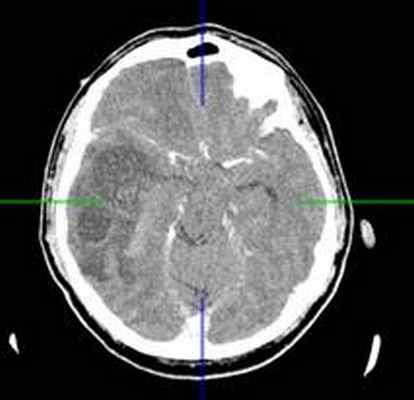

КТ головного мозга с контрастным усилением (24.03.2015): объемное кистозно-солидное образование правой теменно-височно-лобной области. Дислокационный синдром.

22.10.2015 была выполнена операция: микрохирургическое удаление опухоли правой височной доли под интраоперационными навигационным контролем и с интраоперационной фотодинамической терапией.

КТ головного мозга (23.10.2015): не выявило признаков кровоизлияния или каких-либо других хирургических осложнений в области оперативного вмешательства.